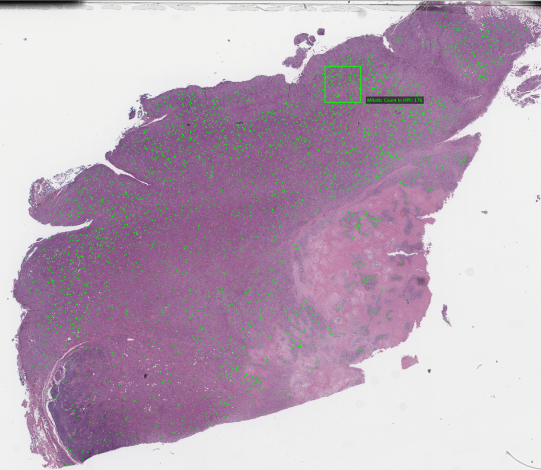

The model results are integrated in the pathologist workflow. The pathologist will receive the information from the model as annotations that are rendered from the generated XML file in a WSI viewer.

Figure 5: A fully annotated whole slide image on the pathologist’s viewer

Refer to caption

Figure 6: Zoomed-in view of an annotated WSI

The pathologists can themselves annotate False Positive and False Negative Examples by adding annotations to their slide viewer. Those feedback annotations get stored in a database that is read out daily. Based on the feedback information new images for fine tuning of the Detection model (3.4) are created. Fine-tuning is performed on a regular basis, dependent on the feedback volume.